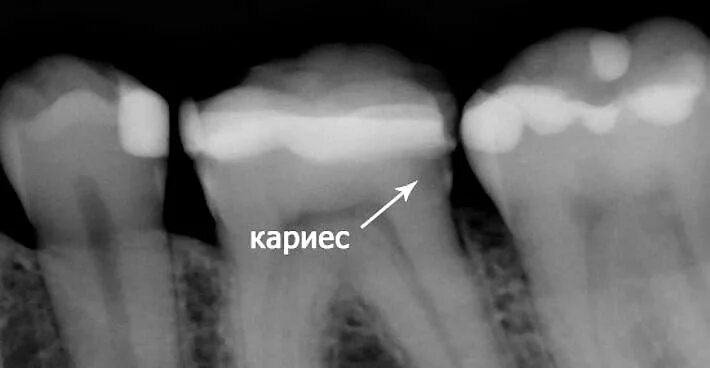

Как понять снимок зуба